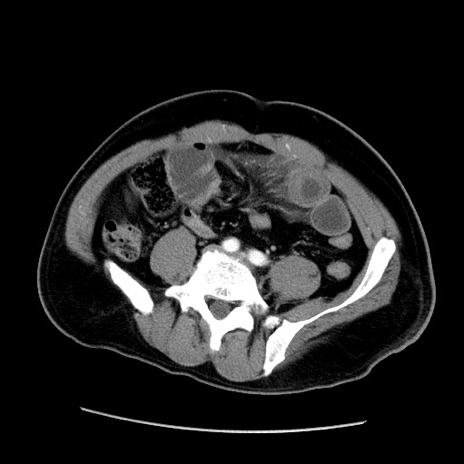

冠状断像

【症例】50歳代男性

【主訴】腹痛

【現病歴】AVMからの被殻出血のため回復期リハ病棟入院中。 本日午後3時頃急に下腹部痛が出現した。

【既往歴】AVM、被殻出血、虫垂炎、高血圧

【身体所見】意識晴明、左半身不全麻痺、会話の理解は良好、36.5°C、腹部:膨隆、全体に板状硬、下腹部正中に圧痛点あり、反跳痛-、筋性防御不明、右下腹部にope scar

【データ】WBC 9400、CRP 0.06